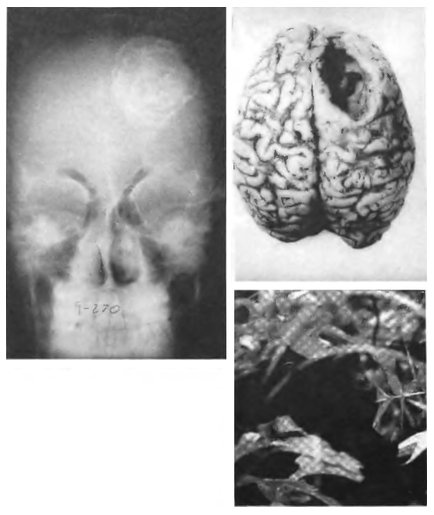

Иногда паразиты ошибаются, и результаты могут оказаться смертельными. Слева вверху: обычно ленточные черви сначала зреют в цистах в промежуточных хозяевах (например, в коровах или свиньях) и лишь потом попадают в организм человека. Но, если их яйца вдруг окажутся в человеческом теле, они будут развиваться и образуют цисту где угодно; часто это происходит в мозгу. Справа вверху: овод отложил свои яйца на голове мальчика, и одна из личинок проникла в мозг. Внизу: хозяевам приходится находить пути защиты от вездесущих паразитов. Так, шимпанзе едят лекарственные растения, чтобы бороться с незваными гостями.